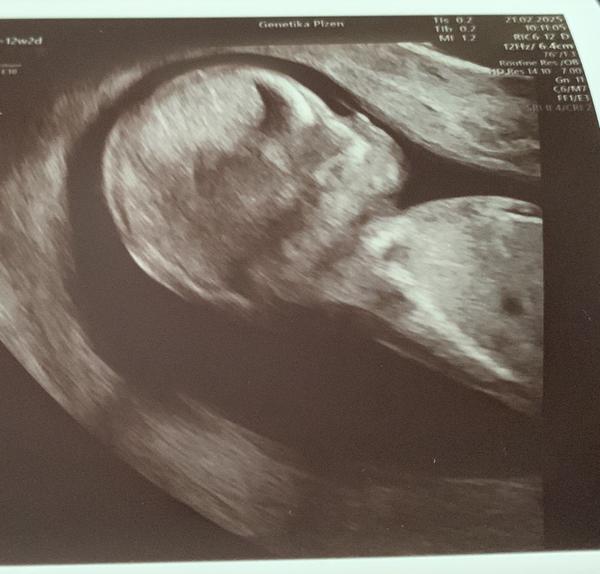

@reeeza tak náš malý měl šíjové projasnění 5,4 a limit je 2,5. Doktor se se mnou bavil v podstatě tak, že je to škoda, protože plod jinak vypadá dobře, ale hned se mnou probíral možnosti případného potratu. Na výsledky jsme čekali 3 týdny, spousta stresu a pláče a je to spokojené, usměvavé miminko. Takže i kdyby tam mělo miminko více tekutiny, nemusí to vůbec nic znamenat. 🙂 Testy jsem si platila neinvazivní a dělali to v Plzni. Tam je na to specializované pracoviště.

@reeeza jinak nase fotky z prvotrim screeningu vypadaly takto..